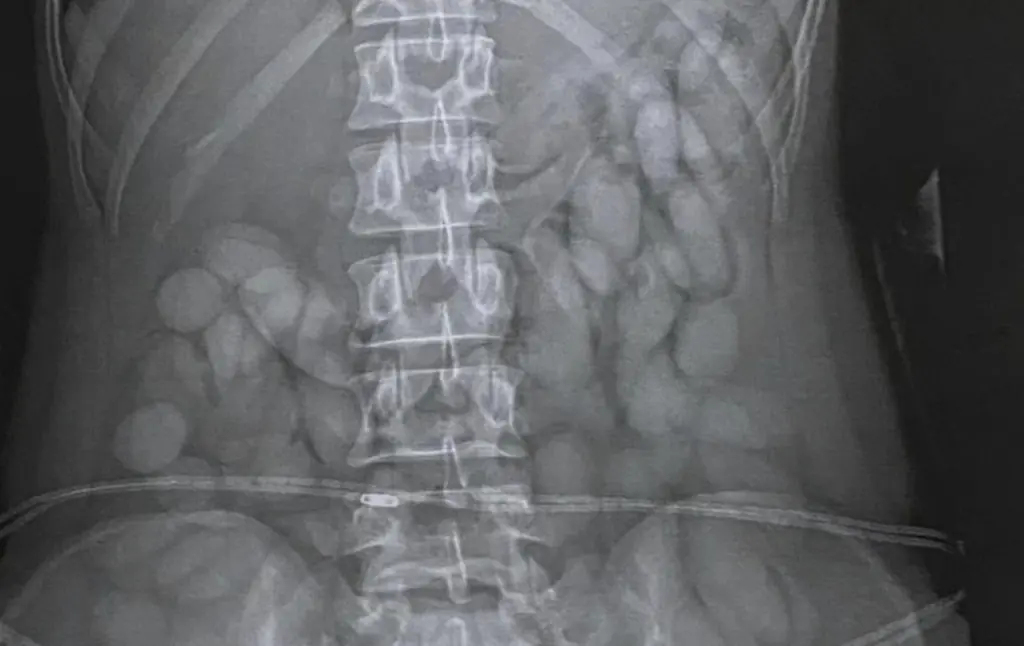

In total, she expelled 68 bullets, which police weighed in at about 850 grams. That’s a lot to carry around in your stomach.

The "bullets" weighed about 850 grams each. Credit: South African Police Service